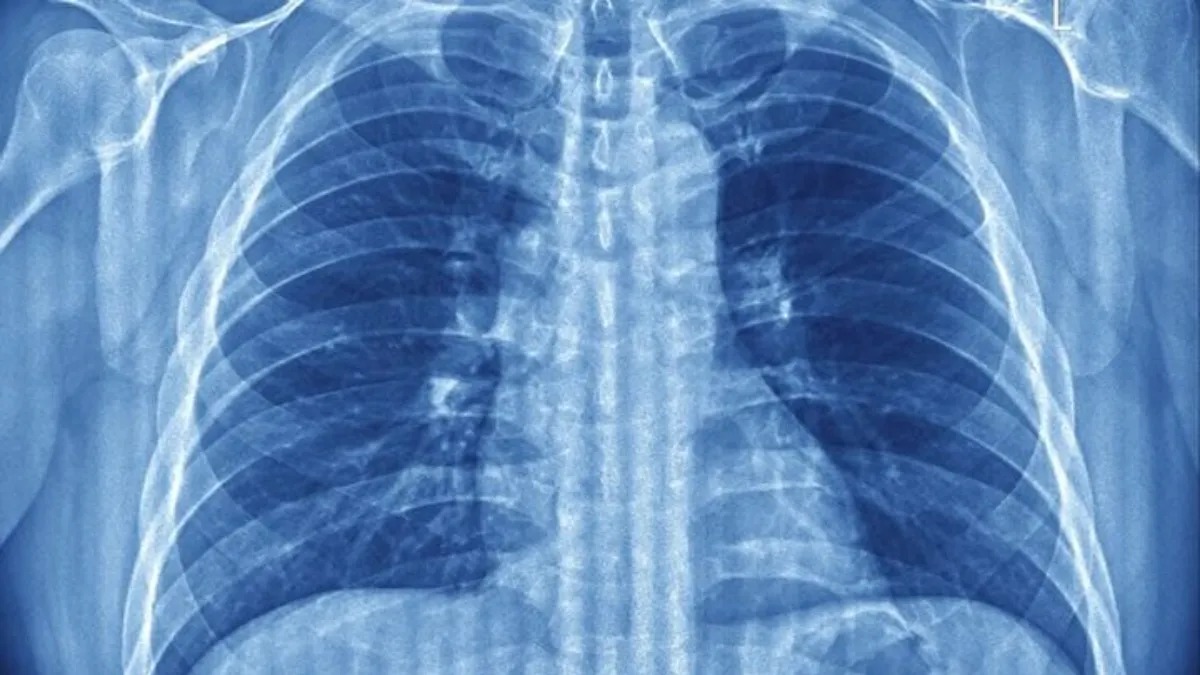

ABŞ-da yerləşən bir tədqiqat qrupu, dərin nəfəs almanın ağciyərlərin çökməsinin qarşısını alan və alveol adlanan hava kisələrini qoruyan təbii bir mexanizm olduğunu ortaya qoyub.

Bu maddə hər dəfə nəfəs alanda hava kisələrinin çökməsinin qarşısını alır və oksigen mübadiləsini qoruyur.

Tədqiqatçıların fikrincə, bu refleksin əsas məqsədi ağciyər səthinin qurumasının və yapışmasının qarşısını almaqdır.